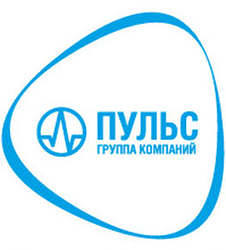

- Двухэнергетическая субтракция (ДЭР)

За один сеанс система делает два снимка с разной энергией излучения. Их компьютерная обработка позволяет получить три независимых изображения: стандартное, только мягких тканей и только костных структур. Это повышает точность диагностики патологий легких и костей без увеличения лучевой нагрузки.